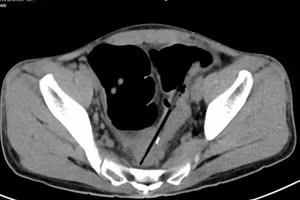

GD&TĐ - Ngày 30/9, tin từ Bệnh viện Đa khoa Trung ương Cần Thơ, các bác sĩ vừa lấy dị vật là hạt hồng xiêm bị bỏ quên nhiều năm trong người bệnh nhân.